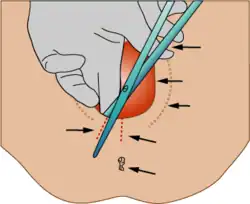

- Cesarean section, or C-section, is the delivery of a baby through a surgical abdominal incision (Abdominal delivery - Abdominal birth - Cesarean section). A C-section delivery is performed when a vaginal birth is not possible or is not safe for the mother or child. Surgery is usually done while the woman is awake but anesthetized from the chest to the legs by epidural or spinal anesthesia. An incision is made across the abdomen just above the pubic area. The uterus is opened, and often brought through the incision after delivery for better visualization. The amniotic fluid is drained, and the baby is delivered. The baby's mouth and nose are cleared of fluids, and the umbilical cord is clamped and cut. After delivery a nursery nurse or pediatrician check the make sure that the baby is breathing and responding. Due to a variety of medical and social factors, C-sections have become fairly common; around 25% of births are performed by C-section. C-sections carry some risks to mother and baby. Compared to a vaginal birth, the risks to mother include increased risk of death, surgical injury, infection, postpartum depression, and hemorrhage, although these are rare. Babies born by c-section are more likely to be admitted to the ICU for breathing problems. Mothers are advised to carefully weigh the risks of C-section versus vaginal birth.